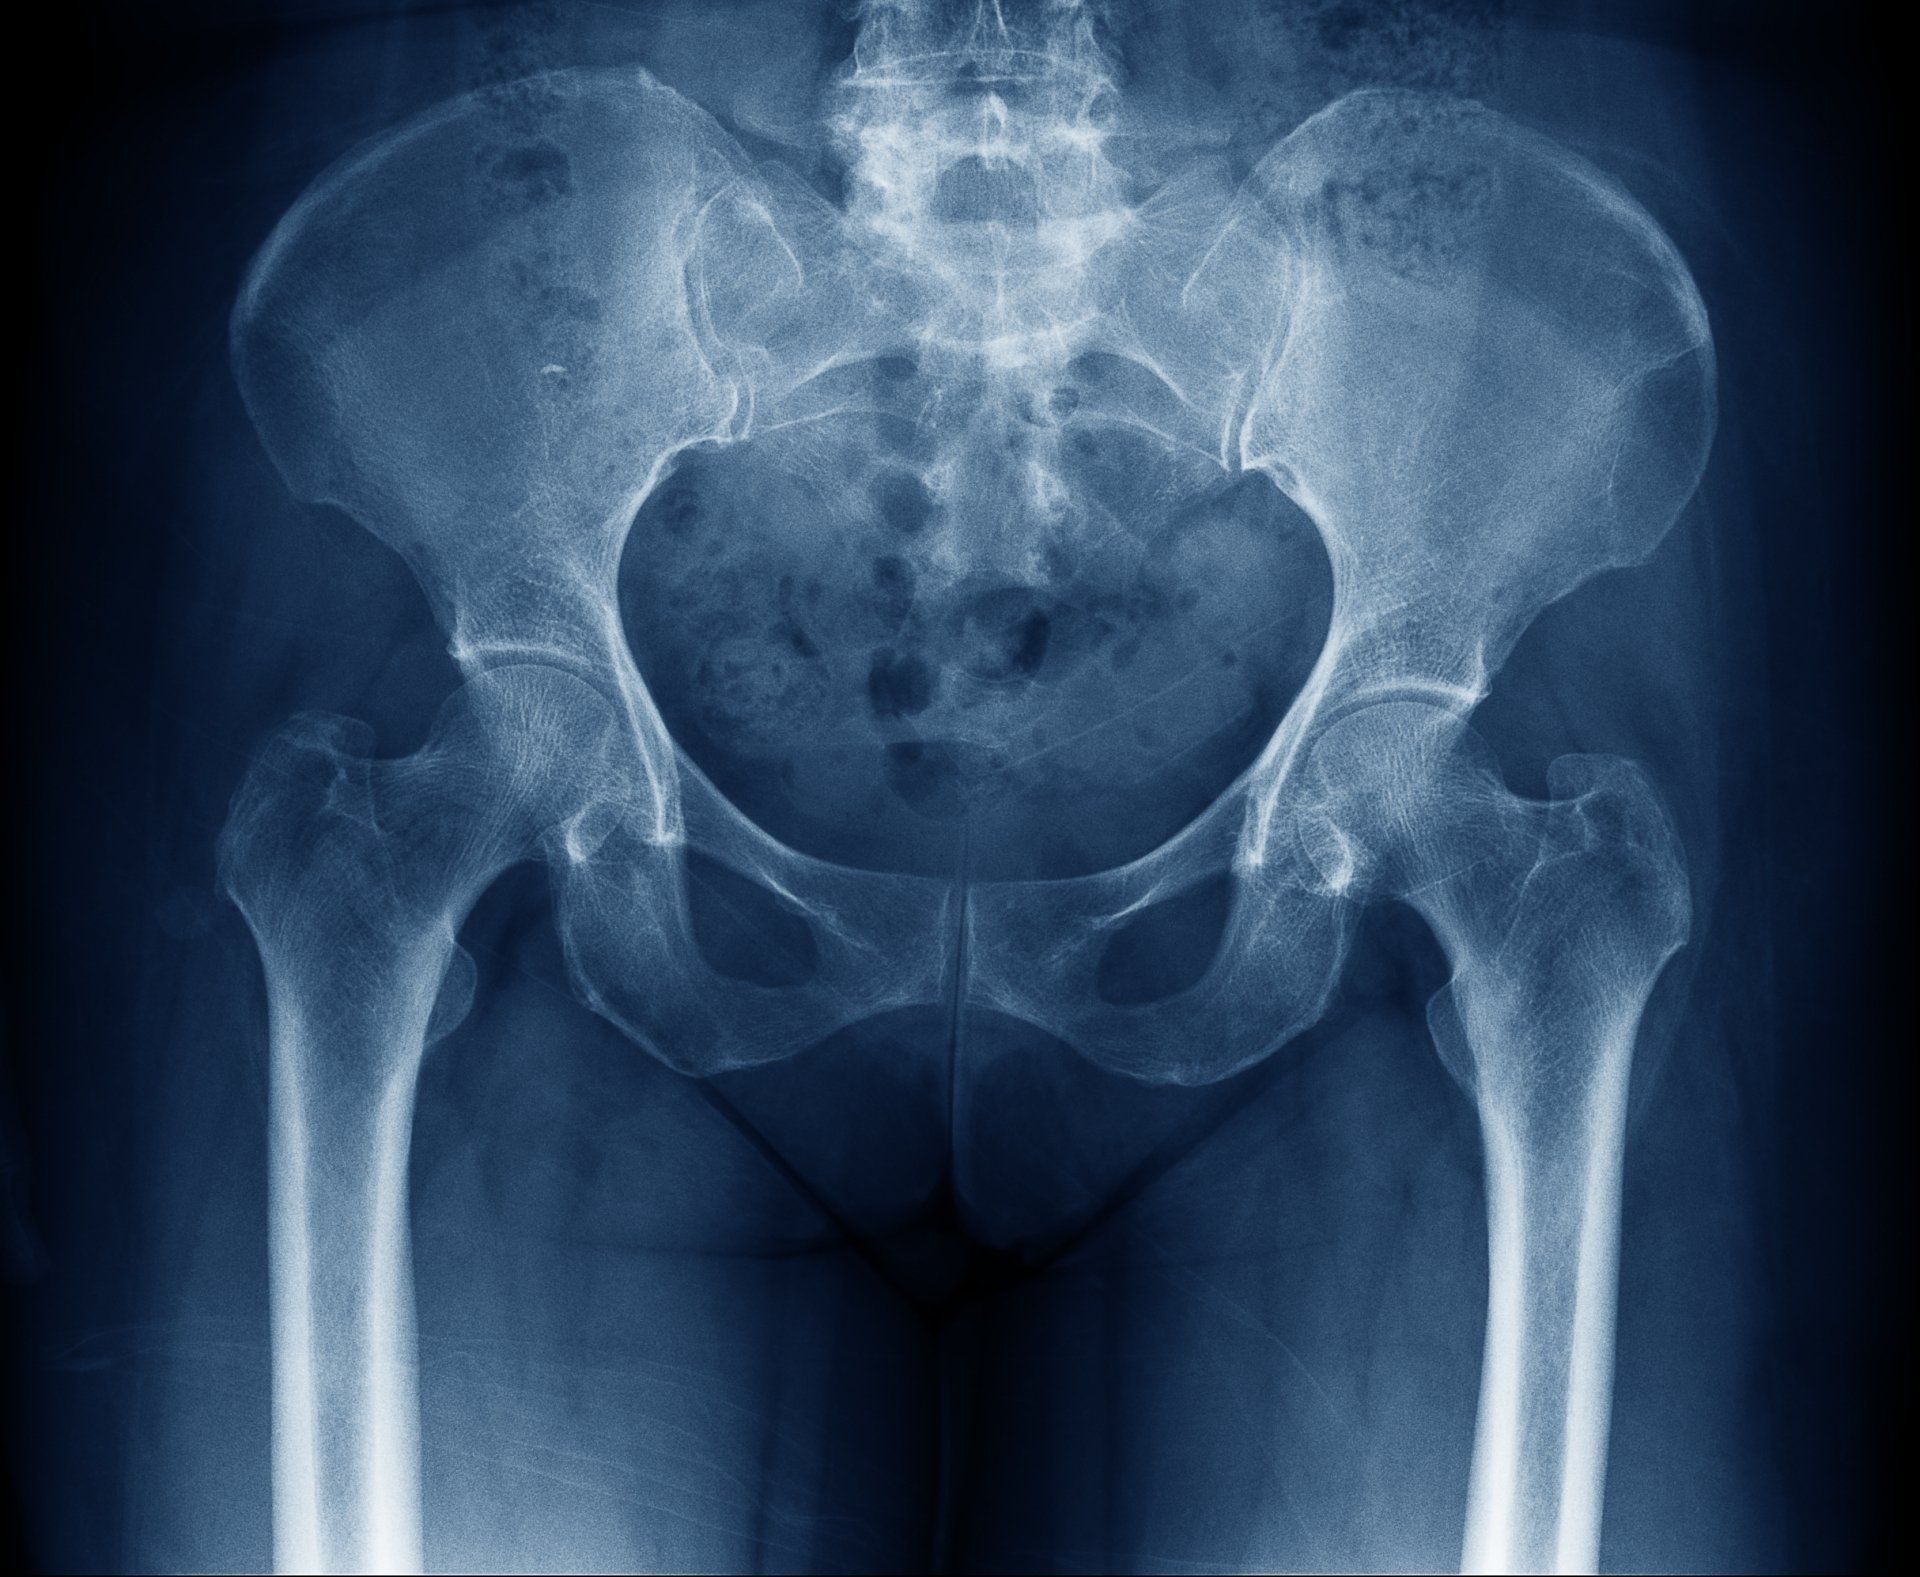

El ácido hialurónico está presente en elevadas concentraciones en el líquido sinovial que baña el interior de las articulaciones. Ayuda a proteger el cartílago articular al absorber los impactos mecánicos a los que está sometida la articulación.

En la artrosis, el peso molecular y la concentración de ácido hialurónico están reducidos.

La administración intraarticular de ácido hialurónico tiene como objetivo restablecer las propiedades biomecánicas del líquido sinovial.